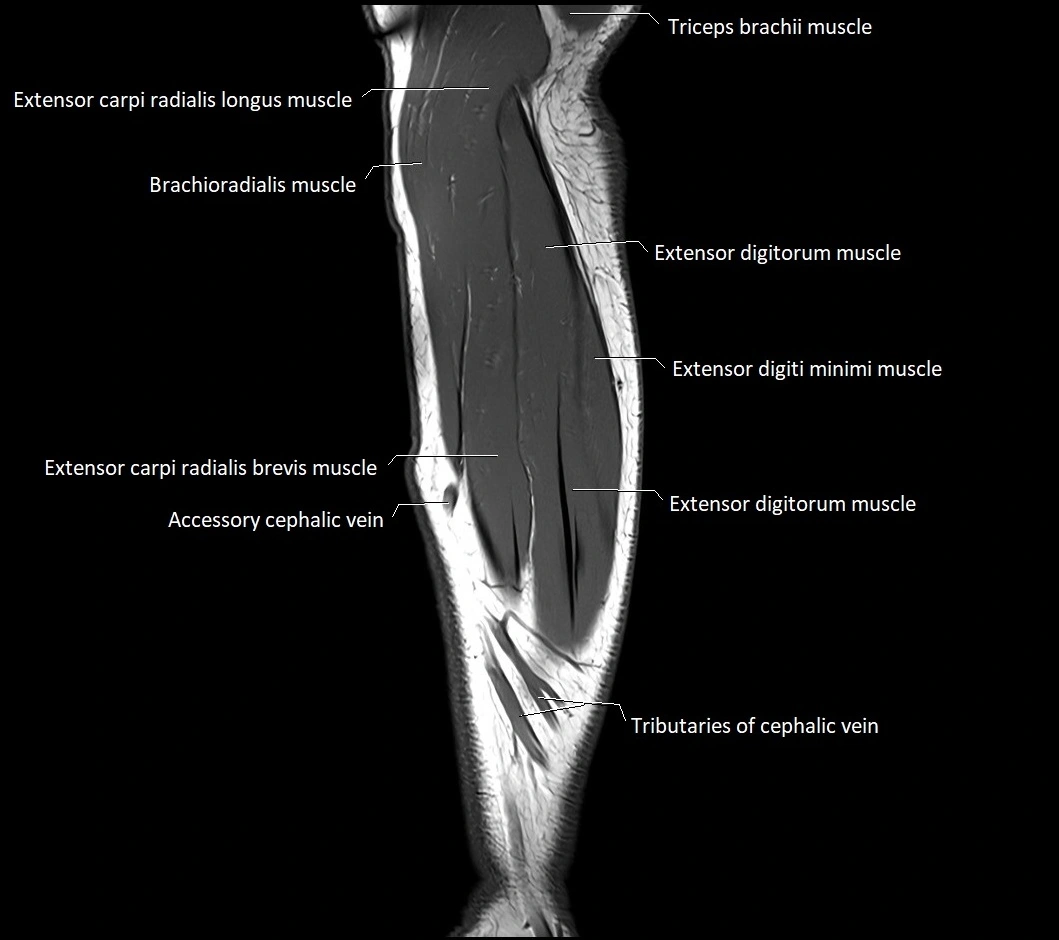

MRI images

image